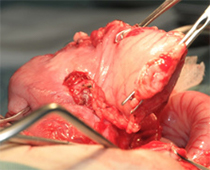

肝臓腫瘍と胆嚢を摘出した写真です。肝臓腫瘍摘出には超音波乳化吸引装置を使用し、かなり安全に手術が可能でした。

胆嚢内にはゼリー状の内容物が詰まっていました。手術後は2日後から食欲も改善し、状態も改善しました。病理検査で肝細胞癌との診断でしたが、手術で切除しきれているとのことで、今後は無治療で経過観察中です。